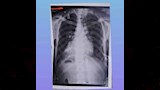

نجح فريق طبي متخصص بمستشفى القلب الجامعي بجامعة أسيوط في إجراء عملية قلب مفتوح معقدة ونادرة، أنقذت حياة مريض يبلغ من العمر 48 عامًا، كان يعاني من حالة طبية فريدة تُعرف باسم "انقلاب وضع الأحشاء الكلي" (Situs Inversus Totalis)، وهي حالة نادرة الحدوث تتراوح نسبتها بين حالة واحدة لكل 10 آلاف إلى 50 ألف شخص.

وكان المريض قد وصل إلى المستشفى في حالة صحية حرجة، حيث تبين أنه يعاني من عيب خلقي نادر تمثل في انعكاس كامل لأعضاء الجسم الداخلية؛ إذ كان القلب في الجهة اليمنى من الصدر والكبد في الجهة اليسرى من البطن، إلى جانب إصابته بمضاعفات خطيرة شملت روماتيزم بالقلب، وضيقًا شديدًا في الصمام الميترالي، وجلطة في الأذين الأيسر، وارتجاعًا حادًا في الصمام الأورطي، مما شكل تحديًا كبيرًا أمام الفريق الطبي نظراً لاحتمالية وجود عيوب خلقية إضافية قد تظهر أثناء الجراحة.